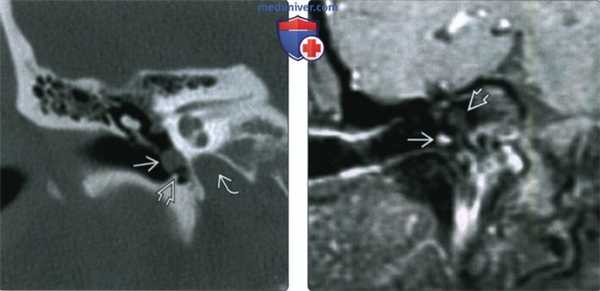

(Слева) КТ с КУ, аксиальная проекция. В области бифуркации правой общей сонной артерии расположено новообразование, равномерно накапливающее контрастное вещество. Опухоль находится между ветвями сонной артерии и смещает внутреннюю яремную вену кзади.

(Справа) КТ с КУ, ранняя артериальная фаза. Опухоль находится в области левой бифуркации и неравномерно накапливает контраст. Она частично заключает в себя сонные артерии, следовательно, относится ко II или III типу по Shamblin. В области правой бифуркации также имеется небольшая параганглиома. Вероятнее всего, заболевание имеет наследственную природу.

(Слева) УЗИ. В области бифуркации общей сонной артерии, между наружной и внутренней артериями, имеется гипоэхогенное образование с четкими контурами. Это небольшое образование было обнаружено случайно: пациенту выполнялась КТ по поводу травмы шеи.

(Справа) Этот же пациент, дуплексное сканирование. Очевидна сосудистая природа опухоли. Частотный анализ (на врезке) показал низкую сопротивляемость опухоли.